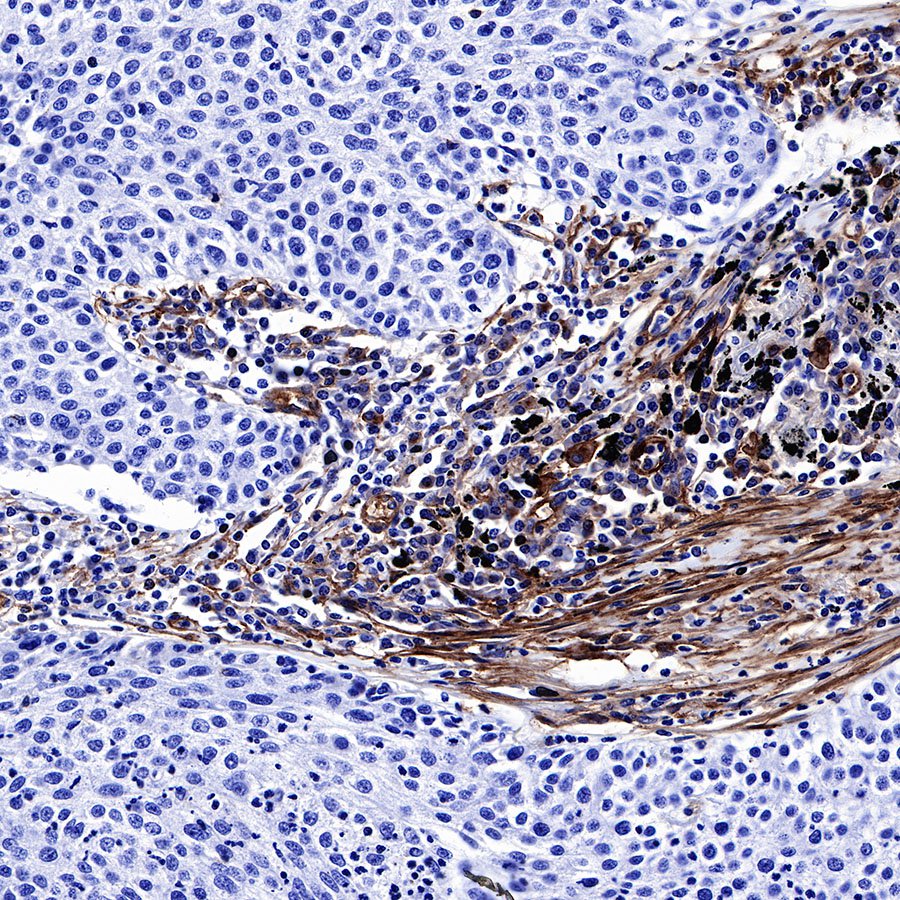

IHC shows positive staining in paraffin-embedded human lung adenocarcinoma. Anti-CD39 antibody was used at 1/500 dilution, followed by a HRP Polymer for Mouse & Rabbit IgG (ready to use). Counterstained with hematoxylin. Heat mediated antigen retrieval with Tris/EDTA buffer pH9.0 was performed before commencing with IHC staining protocol.